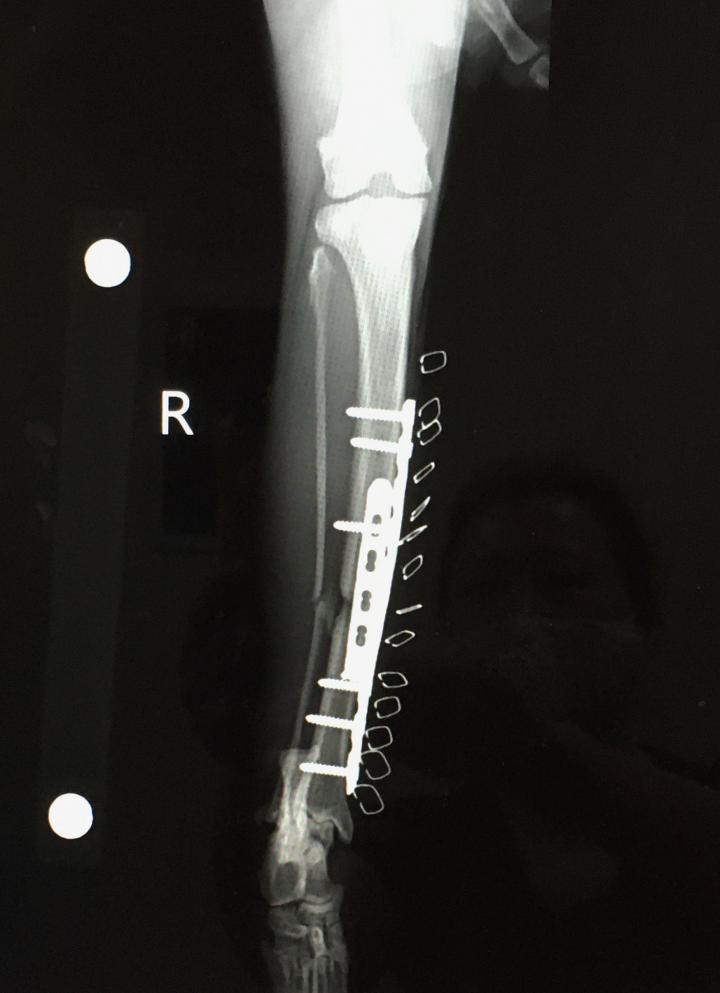

7月26日 午後手術

プレート2本、ボルト8本入れる

7月28日 手術から2日後

地元病院経過観察 止血剤終了、消炎剤継続